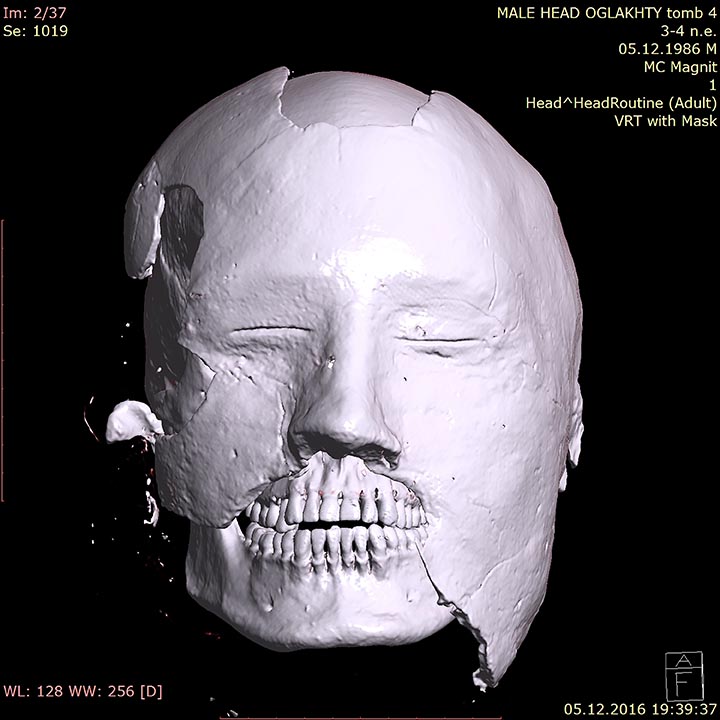

He was from the mountainous region of modern-day Khakasia, aged 25 to 30 when he died 1,700 years ago. Another CT scan showed the face of his gypsum death mask that was all the rage with the ancient Tashtyk people, who were settled cattle-breeders and farmers known for their idiosyncratic burial rituals.

The scan gives it a red punk look but it is believed that the pigtail it was wearing would have been taken off before his death. He is also the only Tashtyk mummy so far found with tattoos. But the most striking and unexpected aspect is a long suture on the side of his face: from the left eye to the ear.

The hole is rather big – 6 by 7 centimetres. It was made postmortem. Expert analysis shows the hole was made by the series of blows with a chisel type or hammer type tool.’ Dr Pankova said: ‘We think that it was made to remove the brain during an elaborate burial rite.’ Likewise, she thinks the facial scar can be explained in similar fashion.

‘Our research is complicated by the fact that we cannot take the mask away from the face (it would cause too much damage) so we must research this stitching using other methods. The archaeologists were intrigued to finally see the face under the death mask, the painting of which ‘adds some unnecessary emotional impressions’

Dr Pankova said the mask ‘has black stripes on a red background, plus the lower part of the mask was somewhat destroyed and man’s teeth can be seen.

‘The computer scan allowed us to see, so to say, three layers – the layer of the mask, the layer of the face without the mask and layer of the skull.’ The face of the woman lying in the same burial chamber – also buried in a fur coat – has not been revealed with a CT scan.